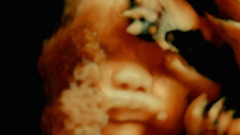

巴黎公立醫院內,重大手術日復一日上演,是震撼的生死瞬間,也是平庸的日常勞動。全片採人類學式的參與觀察,將悚然的血腥手術、內視鏡攝影,搭配醫療人員一派輕鬆的操演,冷靜透析人體內外熟悉又陌生的奇異風景。片名引用五百年前解剖學名著,將血肉敞開於銀幕,宛如鏡像般令人反思生與死、自我與他者的連結。

呂西安.卡斯坦因泰勒:「起初我們使用一般的攝影機拍攝,但對拍出來的素材並不滿意:那些畫面太過尋常而流於俗套,使我們難以貼近病患與外科醫師。於是,我們委託友人派翠克.林登邁爾(Patrick Lindenmaier)打造一款極其微小的攝影機,其微型鏡頭不僅賦予我們最大的移動自由,影像美學更是貼近醫療用的內視鏡。本片幾乎全程使用此設備拍攝,其影像肌理將我們與內外科醫師手中的器械連結起來,而這類素材約占了全片一半的篇幅。我們期望藉由體內和體外影像在景深與視角上的相似性,激發觀眾重新思考內在與外在、自我與他者之間的關係,進而揭示出不同形體之間──無論是人類或非人類、有生命或無生命──那種無限交織的相互依存關係。」